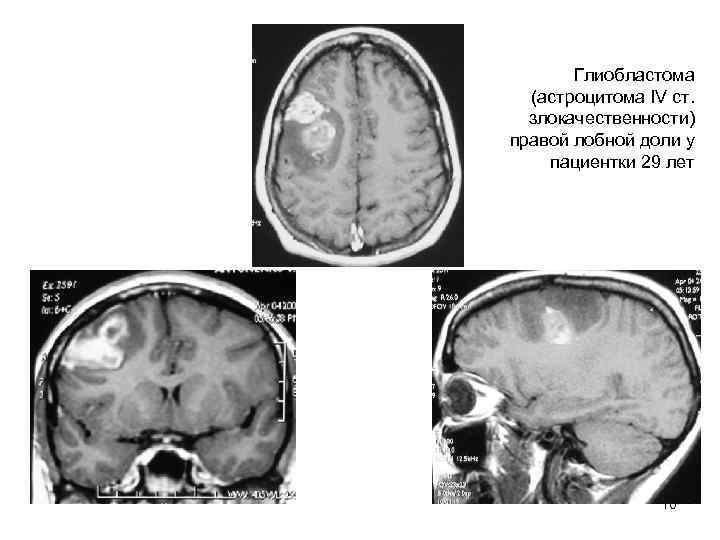

Глиобластома (астроцитома IV ст. злокачественности) правой лобной доли у пациентки 29 лет 10